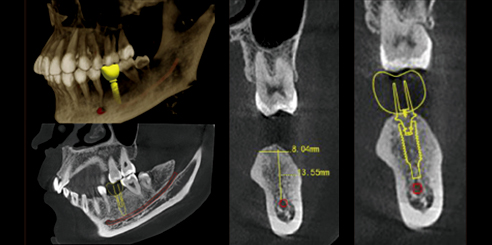

Next, Nerve Detection with Dental CBCT (AI+Nerve)

The system automatically identifies and labels the neural tube within the CT image.

This function simplifies diagnosis and supports more precise surgical planning.